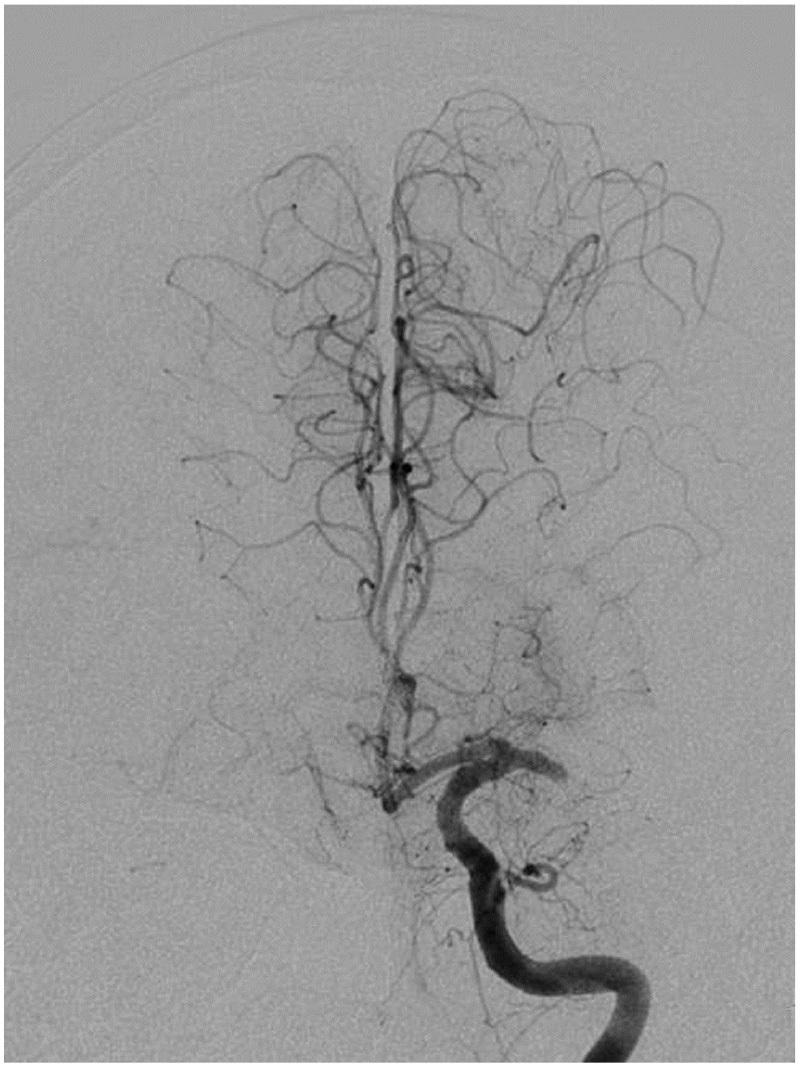

The optional endovascular approach for acute ischemic stroke is unclear. The Trevo stent retriever can be used as first-line treatment for fast mechanical recanalization. The authors developed a treatment protocol for acute ischemic stroke based on the assessment of clot quality during clot removal with the Trevo. This prospective single-center study included all patients admitted for acute ischemic stroke between July 2014 and February 2015, who underwent emergency endovascular treatment. According to the protocol, the Trevo was used for first-line treatment. Immediately after the Trevo was deployed, the stent delivery wire was pushed to open the stent by force (ACAPT technique). Clot quality was assessed on the basis of the perfusion status after deployment of the Trevo; continued occlusion or immediate reopening either reoccluded or maintained after the stent retriever had been in place for 5 min. If there was no obvious clot removal after the first pass with the Trevo, according to the quality of the clot, either a second pass was performed or another endovascular device was selected. Twelve consecutive patients with acute major cerebral artery occlusion were analyzed. Thrombolysis in cerebral infarction score 2b and 3 was achieved in 11 patients (91.7%) and 9 (75%) had a good clinical outcome after 90 days based on a modified Rankin scale score ≤ 2. Symptomatic intracranial hemorrhage occurred in 1 patient (8.3%). The overall mortality rate was 8.3%. Endovascular thrombectomy using the Trevo stent retriever for first-line treatment is feasible and effective.

急性缺血性卒中的选择性血管内治疗方法尚不清楚。Trevo支架取栓器可作为快速机械再通的一线治疗方法。作者基于使用Trevo取栓过程中对血栓质量的评估,制定了一种急性缺血性卒中的治疗方案。这项前瞻性单中心研究纳入了2014年7月至2015年2月期间因急性缺血性卒中入院并接受急诊血管内治疗的所有患者。根据该方案,Trevo被用作一线治疗。在部署Trevo后,立即用力推送支架输送钢丝以打开支架(ACAPT技术)。根据Trevo部署后的灌注状态评估血栓质量;持续闭塞或立即再通,在支架取栓器放置5分钟后要么再次闭塞要么保持通畅。如果使用Trevo首次取栓后没有明显的血栓清除,根据血栓质量,要么进行第二次取栓,要么选择另一种血管内装置。对连续12例急性大脑中动脉闭塞患者进行了分析。11例患者(91.7%)达到脑梗死溶栓评分2b和3分,90天后基于改良Rankin量表评分≤2,9例(75%)患者获得良好的临床结局。1例患者(8.3%)发生有症状性颅内出血。总死亡率为8.3%。使用Trevo支架取栓器进行一线治疗的血管内血栓切除术是可行且有效的。